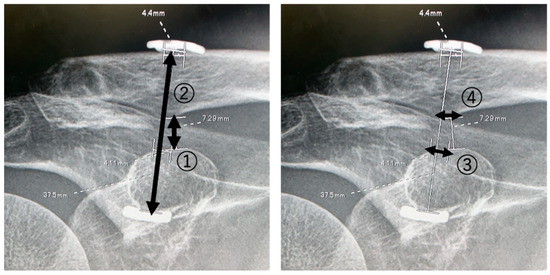

| Coracoclaviclar Distance (mm) | Dog Bone Distance (mm) | |||||||||

|---|---|---|---|---|---|---|---|---|---|---|

| Patient | 1 w | 3 m | 6 m | 9 m | 12 m | 1 w | 3 m | 6 m | 9 m | 12 m |

| 1 | 8.0 | 7.3 | 8.3 | 8.0 | 8.6 | 33.9 | 37.5 | 36.3 | 36.7 | 37.0 |

| 2 | 4.4 | 4.70 | 5.4 | 5.8 | 6.3 | 32.1 | 30.1 | 31.4 | 30.9 | 32.3 |

| 3 | 4.4 | 4.8 | 5.0 | 5.2 | 4.9 | 25.3 | 27.2 | 27.2 | 27.7 | 28.7 |

| 4 | 10.0 | 11.4 | 12.3 | * | 13.3 | 48.5 | 50.8 | 53.2 | * | 51.9 |

| 5 | 5.4 | 8.0 | 8.7 | 7.7 | 8.3 | 42.7 | 42.2 | 42.1 | 42.3 | 44.1 |

| 6 | 6.6 | 8.9 | 9.5 | 10.1 | 10.3 | 43.7 | 45.1 | 45.9 | 46.1 | 45.7 |

| mean | 6.5 ± 2.0 | 7.5 ± 2.5 | 8.2 ± 2.7 | 73 ± 1.9 | 8.6 ± 3.0 | 37.7 ± 8.7 | 38.8 ± 9.0 | 39.3 ± 9.6 | 36.7 ± 7.7 | 40.0 ± 8.8 |

| Bone Hole Size (mm) | ||||||||||

| Superior Coracoid | Inferior Clavicle | |||||||||

| 1 | 2.4 | 4.1 | 4.5 | 5.5 | 5.8 | 2.4 | 4.2 | 4.6 | 6.0 | 6.1 |

| 2 | 2.4 | 2.8 | 3.0 | 3.2 | 4.6 | 2.4 | 4.5 | 5.6 | 4.8 | 7.0 |

| 3 | 2.4 | 3.8 | 3.9 | 4.0 | 4.2 | 2.4 | 5.8 | 5.7 | 5.5 | 5.8 |

| 4 | 2.4 | 3.0 | 3.5 | * | 5.0 | 2.4 | 3.0 | 3.5 | * | 5.0 |

| 5 | 2.4 | 4.3 | 4.6 | 4.6 | 5.0 | 2.4 | 4.1 | 3.8 | 4.4 | 4.4 |

| 6 | 2.4 | 4.5 | 5.5 | 5.1 | 5.6 | 2.4 | 4.5 | 6.3 | 6.4 | 5.6 |

| mean | 2.4 | 3.7 ± 0.7 | 4.2 ± 0.9 | 4.9 ± 0.9 a | 5.0 ± 0.6 a | 2.4 | 4.3 ± 0.9 | 4.9 ± 1.1 | 5.4 ± 0.8 | 5.6 ± 0.9 a |